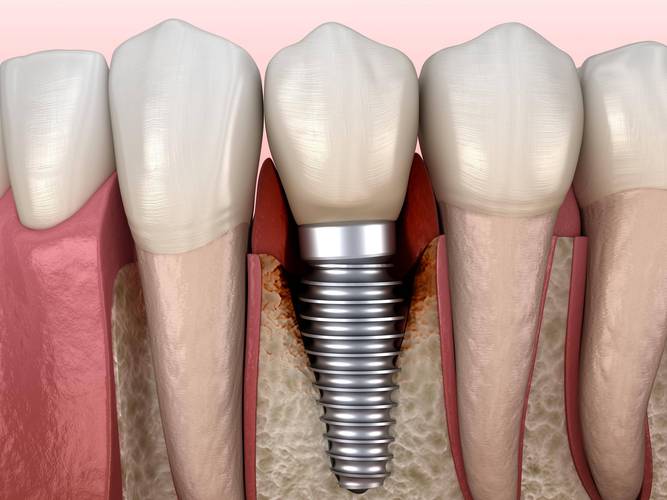

上颌第一前磨牙缺失后,若不及时修复,可能导致邻牙(尖牙和第一磨牙)向缺牙区倾斜,对颌牙(下颌第一前磨牙)伸长,进而引发咬合紊乱、食物嵌塞、牙周问题等,种植牙因其“仿生”特性(独立牙根,不损伤邻牙)、高稳定性和接近天然牙的咀嚼效率,成为上颌5牙缺失的首选修复方式,与活动义齿和固定桥相比,种植牙无需磨损邻牙,能更好地恢复牙槽骨的生理刺激,防止骨吸收。

上颌5种植牙治疗周期通常为3-6个月,分四阶段完成:①术前检查与设计:通过CBCT评估牙槽骨厚度、高度及与上颌窦的距离(理想距离≥2mm,若不足需行上颌窦提升术),口内扫描获取牙列模型,结合咬合分析制定种植方案,必要时采用数字化导板辅助种植,将误差控制在0.1mm内,提高种植体植入精度。②种植手术:局部麻醉下,在缺牙区牙龈做弧形切口,剥离黏骨膜暴露牙槽骨,使用专用种植机逐级备洞(直径3.5-4.5mm,深度10-13mm,避免穿通上颌窦),将纯钛种植体(生物相容性极佳)植入牙槽骨,植入扭矩通常≥35N·cm(确保初期稳定性),生理盐水冲洗后缝合切口,术后7天拆线。③骨结合期:种植体与牙槽骨形成“骨整合”,这是种植成功的关键,上颌骨因血供相对下颌差,骨结合时间需4-6个月,期间避免种植区咀嚼受力,可佩戴临时义齿美观。④牙冠修复:骨结合完成后,行二期手术暴露种植体,安装愈合基台,2周后牙龈成型,取模制作全瓷或烤瓷牙冠(全瓷冠美观度更佳,生物相容性好),试戴调整咬合后粘固完成修复,最终实现“以假乱真”的咀嚼效果。